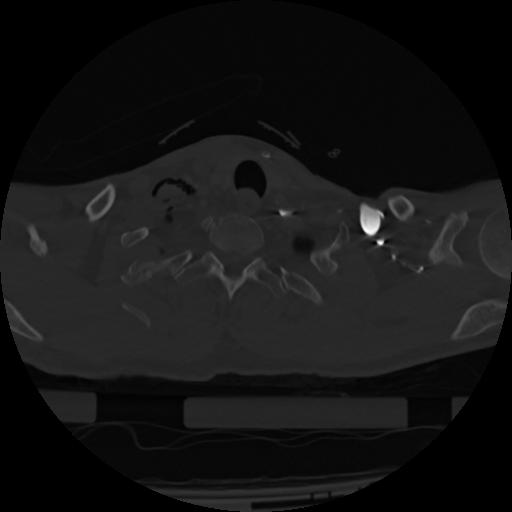

22 ANGIO,CE,Vol,0.5,ANGIO,,